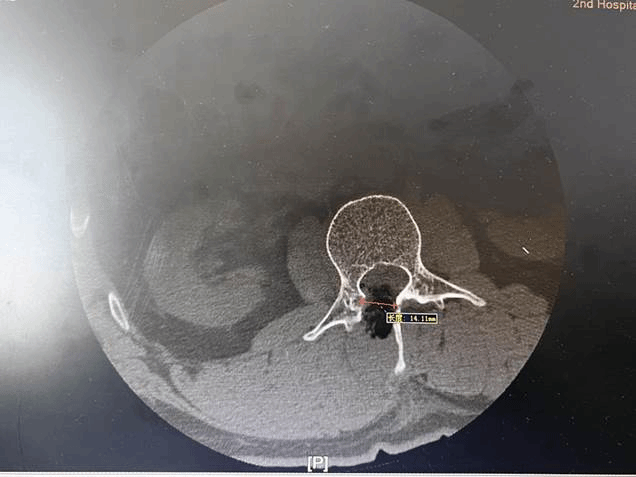

入院后,经过全面检查发现,肿瘤位于腰二锥体后方的椎管内,大小约1.6厘米。孙颖教授带领团队经过讨论决定为其进行显微镜下经脊柱微通道完整切除神经鞘瘤。

孙颖教授介绍,神经外科脊髓脊柱手术都是在显微镜下完成,具有术野清晰、创口小、出血少、病变显露清楚、病变全切率高、对正常组织损伤小、病人恢复快、痛苦小、花费少的特点。此例手术需要在皮肤上做一个不到2厘米切口,通道直径仅为1.4厘米,对椎旁肌肉剥离及损伤小,尤其对脊柱骨质破坏少,仅仅磨除直径约1.5厘米骨窗,相当于在脊柱上打了一个指甲盖大小的“窟窿”,不破坏脊柱稳定性,不用对脊柱进行外固定。由于脊柱稳定性没有破坏,无需脊柱钉棒系统进行固定,大大减少患者医疗费用,住院周期短,而且因为切口小,所以只对切口进行皮内缝合,患者术后无需拆线,术后第二天患者可以下地活动,术后第三天就可以出院。